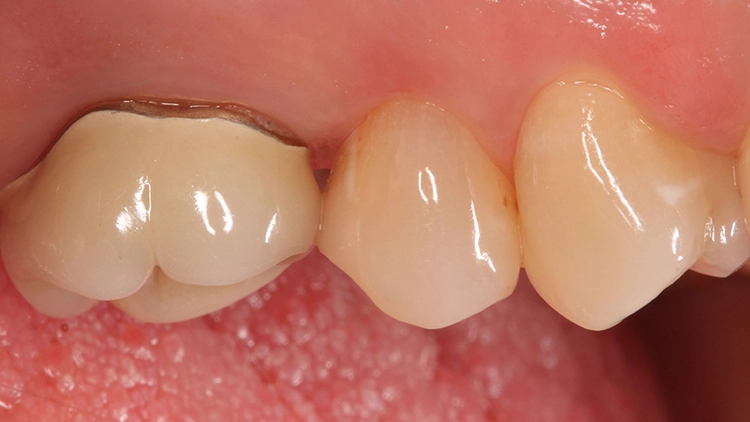

Die Patientin bat damals um einen Austausch des Goldinlays, da ihr keine Möglichkeiten einer Nacharbeitung am Inlayrand angeboten werden konnten. Die Inlayversorgung zeigte sich sehr weit in den Approximalraum ausgedehnt (Abb. 11 und 12), was nach Aussage der Patientin an der damaligen Indikation eines Lückenschlusses zwischen den Zähnen 25 und 26 lag.

Nach Entfernung des Goldinlays zeigte sich eine kariesfreie Kavität, die lediglich nachfiniert werden musste. Im Zuge dieses Arbeitsschrittes wurde auch die Klebefläche angefrischt. Aufgrund der vorangegangenen Federrandpräparation ergab sich eine für eine Keramikversorgung (die als Alternative diskutiert worden war) sehr ungünstige Gestaltung des approximalen Kastens.

Ein Nachpräparieren in Richtung einer planen Stufe würde den approximalen Kasten unnötig vertiefen. Ein zervikaler Aufbau in Form einer Kavitätenbodenelevation [13,15,24–26] würde dieses Problem zwar lösen, aber dann auch die berechtigte Frage aufwerfen, warum bei einem so klein dimensionierten Defekt der Rest der Kavität nicht auch gleich mit Komposit versorgt wird.

Approximale Überhänge, die wie im vorliegenden Fall labortechnisch leicht mit dem Goldinlay zu überbrücken sind, sind bei Keramikmaterialien nicht sonderlich beliebt: Hier werden häufig 1,5 mm als Maximum der Extension angegeben. Ein Problem, welches bei Komposit – eine hohe Biegebruchfestigkeit des Materials [9] und eine suffiziente Lichtpolymerisation einmal vorausgesetzt – weniger im Vordergrund steht.